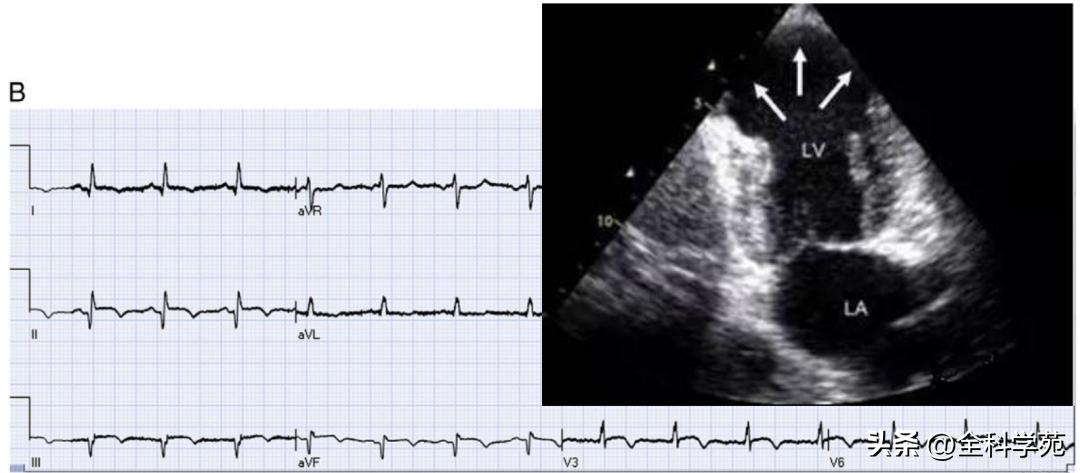

1. 心尖肥厚型心肌病

(1)患者女性,76岁。两个月前爬山时感胸闷、憋气,无放射性疼痛,休息几分钟后缓解。无心悸、气促、黑矇和晕厥,未予诊治。1周前因搬家劳累再发胸骨后闷痛,憋气,遂就诊我院

(2)既往高血压、高脂血症10余年,心房颤动2年

(3)心电图示下壁导联及胸导联T波倒置

(4)行心脏彩超检查提示左房增大,室间隔及左室壁厚度呈渐进性增厚,以心尖部为著(中间段厚18mm,心尖部厚24.5mm),室间隔运动幅度轻度减低,左室射血分数正常

(5)完善冠脉造影,结果示:LM、LAD、LCX无病变,RCAm管腔不规则,狭窄率为50%,并取左室室壁处心肌组织活检

(6)活检结果回报组织学染色下可见排列紊乱、肥大的心肌细胞

- 机制:心尖部心肌局部肥厚导致QSR波向量向左前增大,导致除极方向偏离,造成左胸导联R波增高,同时复极异常,呈明显的心前区(V3~V4导联)T波倒置

- 心肌缺血时无明显R波增高,T波倒置常位于广泛胸前导联,无特异性